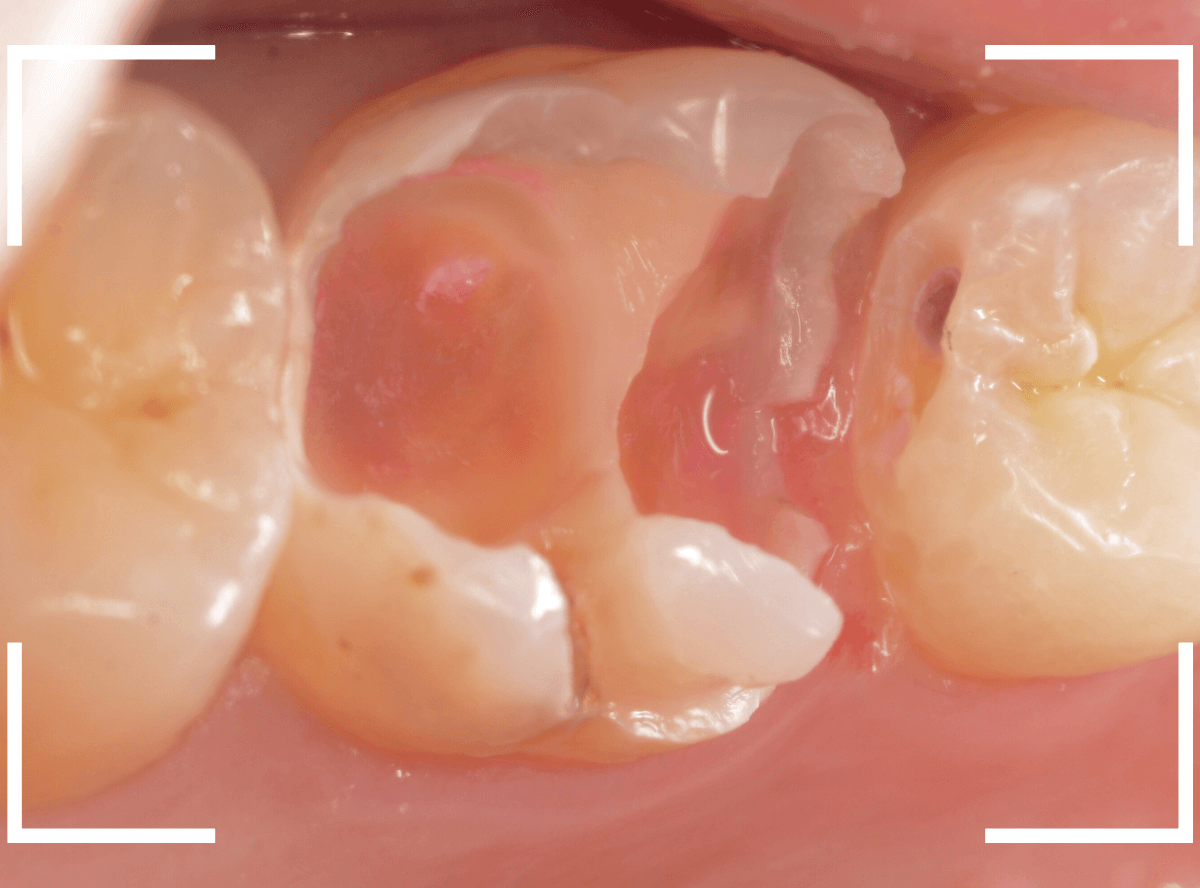

Case.11 外れたつめものの中は、ひどい虫歯

「上の奥歯のつめものが外れた」という訴えで来院された患者さんの例です。

つめものの外れてしまったつめものの中が虫歯になっているのが見えます。

レントゲン写真で確認します。

赤いラインが虫歯、青いラインが歯の神経です。

現在、つめてあるレジンの中まで虫歯が大きく進行し、ほぼ神経まで達しているのがわかります。

虫歯の治療を開始します。

奥につめてあるレジンも除去して中を確認します。

さらに慎重に虫歯を除去します。

手前の歯まで虫歯が進行しているのがわかります。

全ての虫歯を除去したところです。

薄皮一枚、神経ギリギリのところで虫歯を食い止められました。

しばらくは、お薬をつめて経過観察が必要です。

今回、つめものが外れてしまったのは、つめものの中が虫歯になったせいだと考えられます。

今回は、つめものが外れたのが受診のきっかけになったのが不幸中の幸いでした。